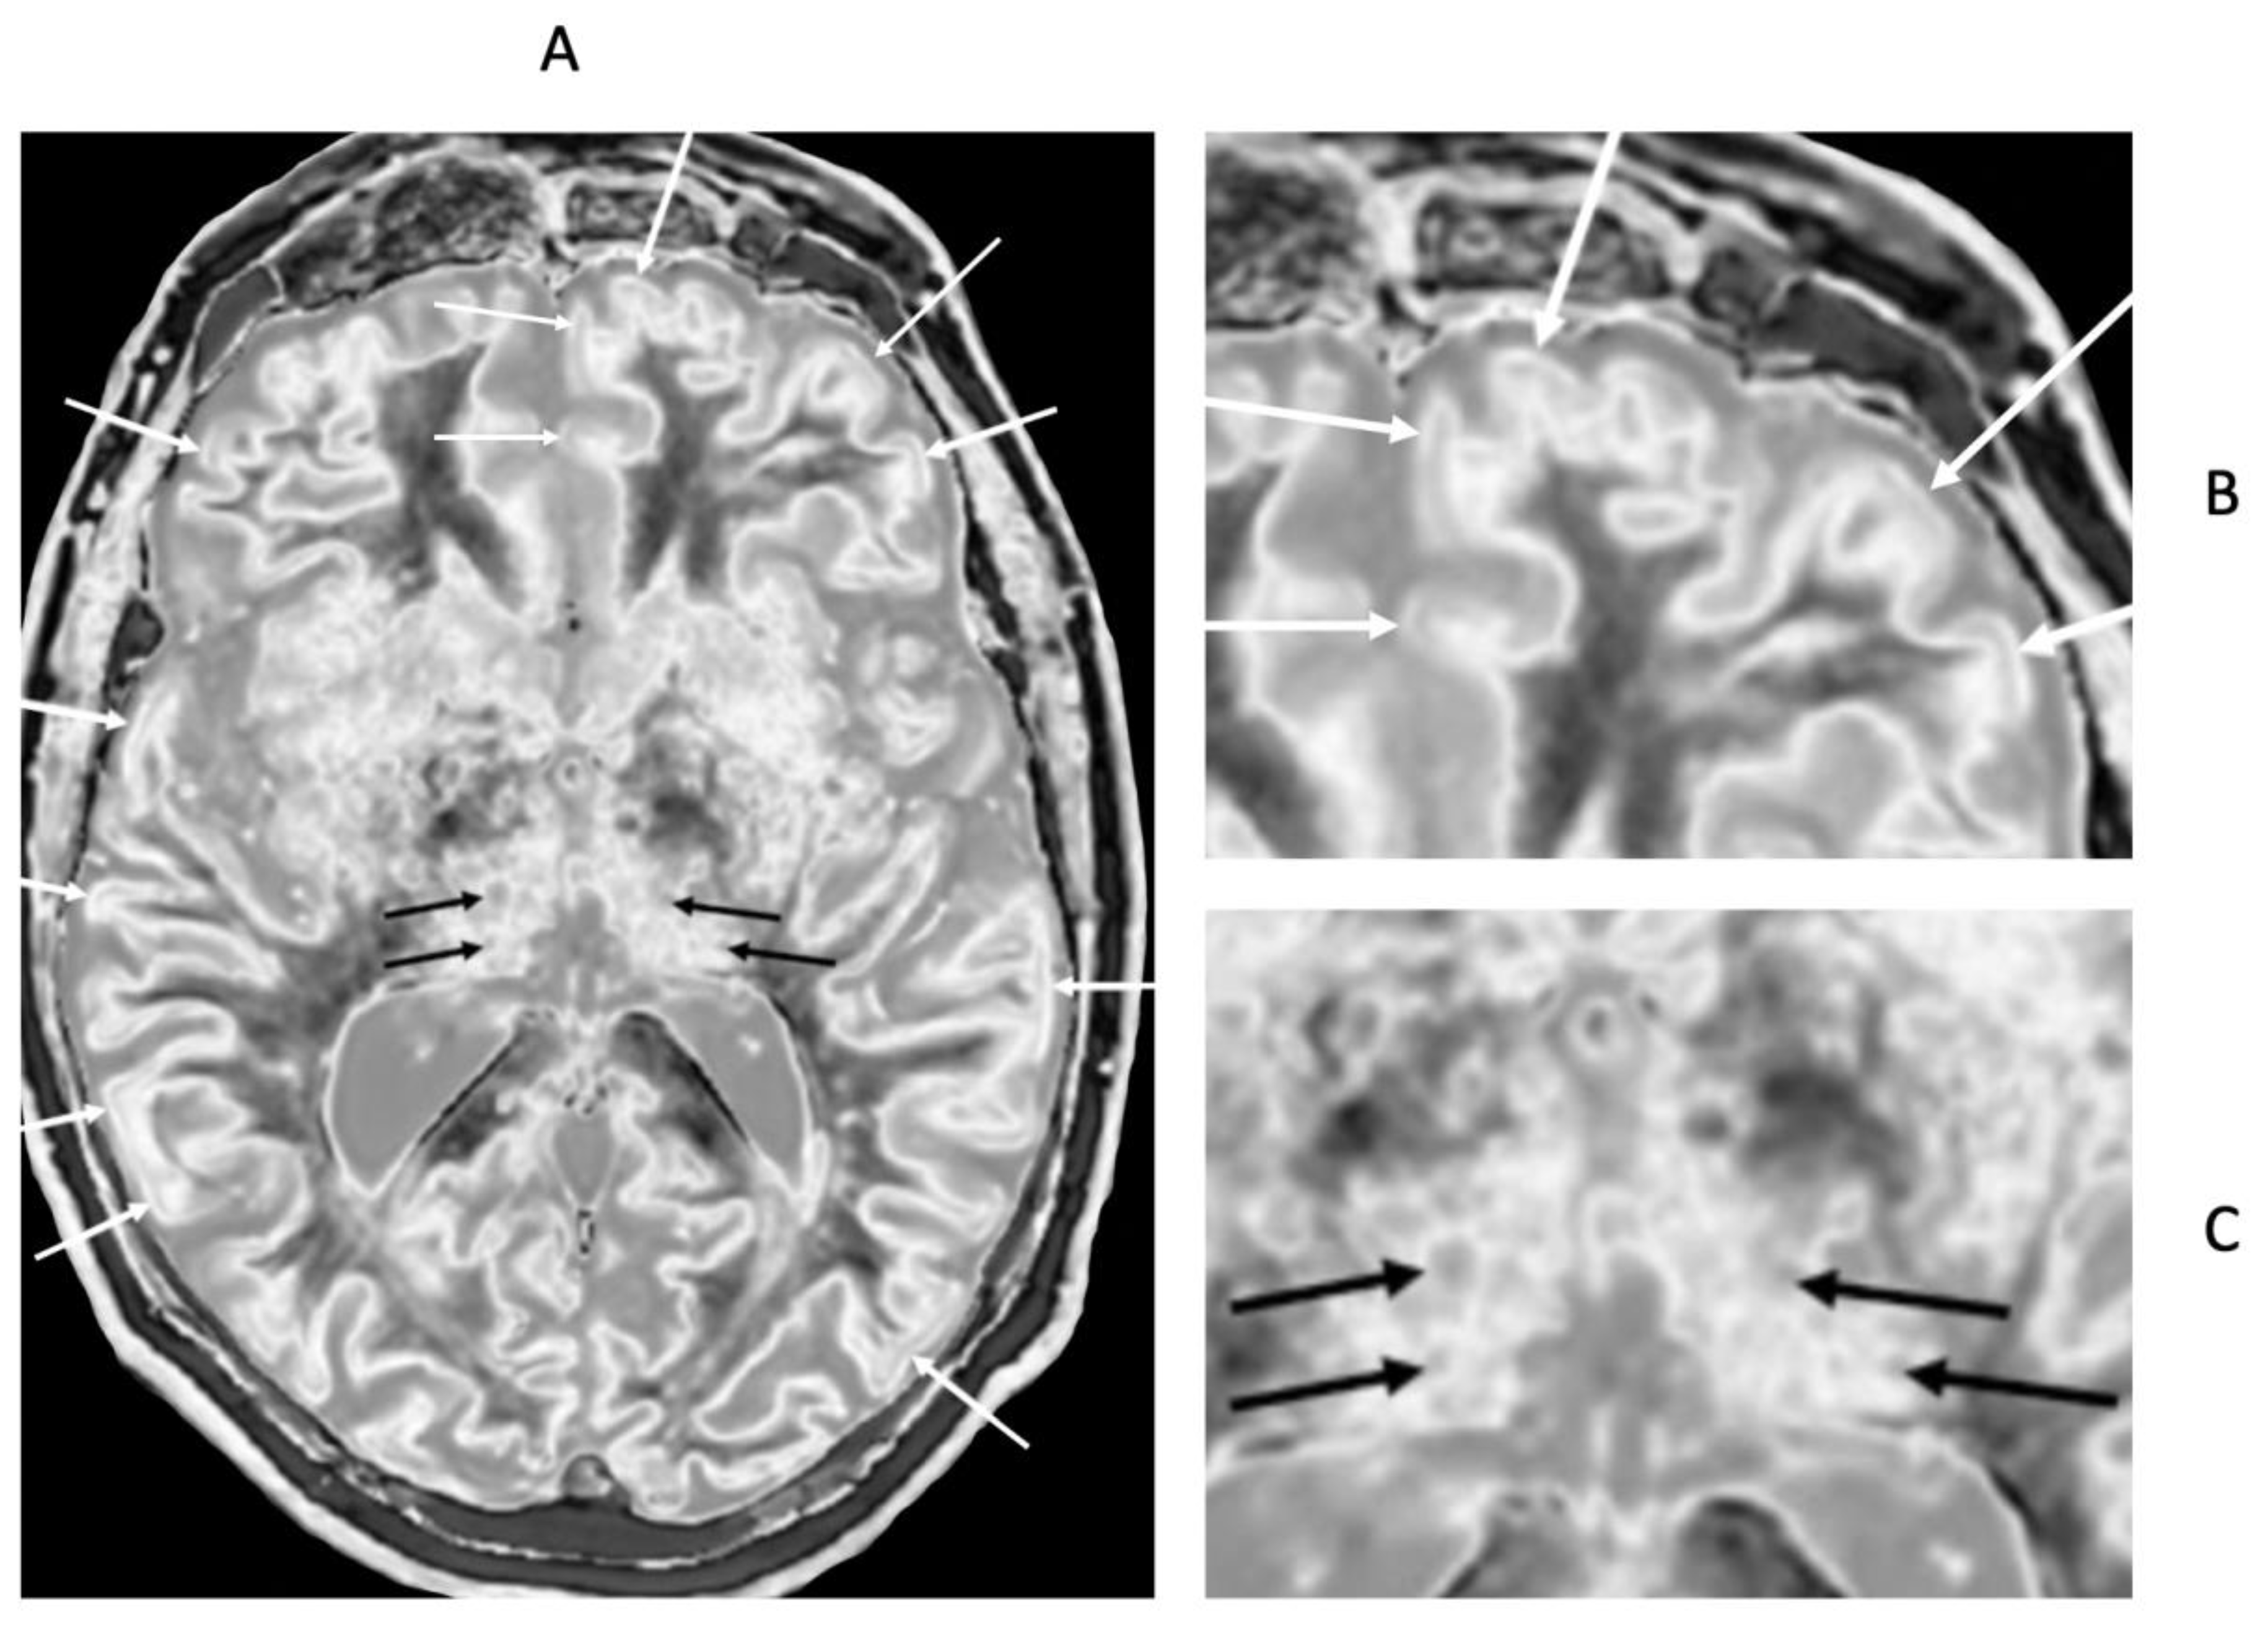

Figure 20.

72-year-old male patient with Parkinson’s disease. 2D narrow mD dSIR (T

1-BLAIR) image (A) with insets of anterior left cortex (B) and thalami (C). There is high signal in the superficial layer of the cortex at multiple sites (bilaminar cortex signs) which are more obvious on the inset (white arrows) (B). There are circular appearances in the thalami, putamen and heads of the caudate nuclei (bubble signs) which are more obvious on the inset (e.g., black arrows) (C). The bubble sign is due to focal reductions in T

1 probably from the presence of free iron. The thalamic signal is slightly higher medially compared with laterally unlike the appearance of the normal thalamus in the 18-year-old patient shown in

Figure 12B.